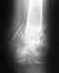

Добрый вечер! Пожалуйста помогите! У моей мамы перелом нижней трети большеберцовой кости! Ей сделали операцию, поставили штырь и винт. 2 месяца находилась в гипсе, но результаты нулевые, так как сместился штырь в голеностоп. Сделали повторную операцию,наложили гипс, прошел месяц, рентгеноконтроль показал, что кость не срастается, смещение отломка. Врач назначил элекрофорез и выписал препарат миакальцик и кальций Д3 никомед.Что вы посоветуйте? Пожалуйста ответьте, с уважением Лариса!

Покажите снимки, ситуация не очень понятна. Если фиксация несостоятельна, то электрофорез и прочее проблему не решат.